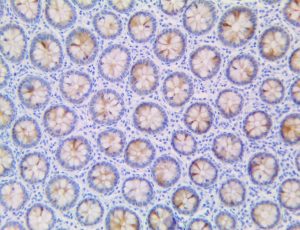

The first cytokines released are interleukin 1β (IL-1β) and tumor necrosis factor-α (TNF-α), which attract a variety of circulating white blood cells (WBCs) to the infection site, including neutrophils, monocytes, macrophages, and natural killer (NK) cells. This response, along with the antipathogenic chemicals released by these cells (i.e., complement), comprise the innate immune response. These cells directly attack the invading pathogen and also release additional cytokines, chief among them interleukin-1 and 6 (IL-6). IL-6 is essential for invoking the adaptive immune response, which calls T-cells, B-cells, and T helper (Th) cells to the infection site. IL-6 also stimulates further recruitment, proliferation and activation of macrophages.

It is the ICU physician who is most likely to witness one of the deadliest manifestations of the abnormal immunological response, the cytokine storm syndrome (CSS). This response is also referred to by some as the cytokine release syndrome (CRS). CSS is characterized by continuous activation and expansion of macrophage and lymphocyte populations, which secrete large amounts of cytokines, causing the cytokine storm. This massive cytokine release is akin to hemophagocytic lymphohistiocytosis (HLH) disease, a syndrome characterized by initial unchecked and persistent activation of cytotoxic T lymphocytes and NK cells.